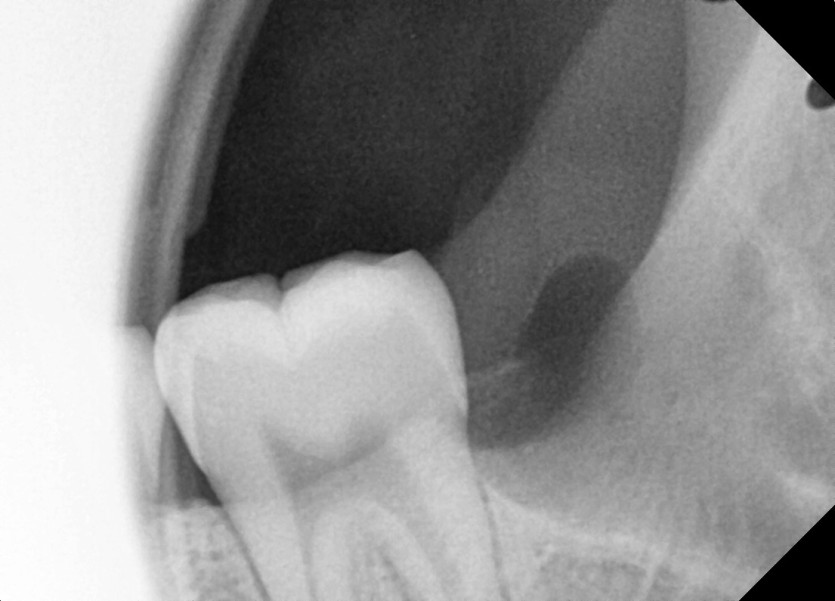

#28,29(과잉치),38 사랑니 발치

구강 외과 전문의가 당일 발치했습니다.